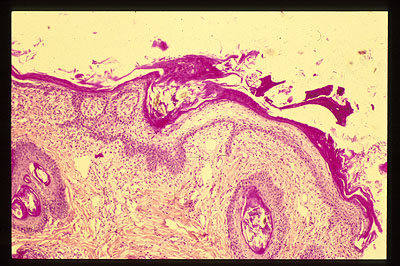

Photo 15 (Hémalun Eosine X 100) : dans certains cas, c’est la parakératose diffuse

de l’épiderme et des infundibula folliculaires qui prédomine le tableau histologique.

Légendes de la Photo 15:

- Parakératose épidermique (coussinet)